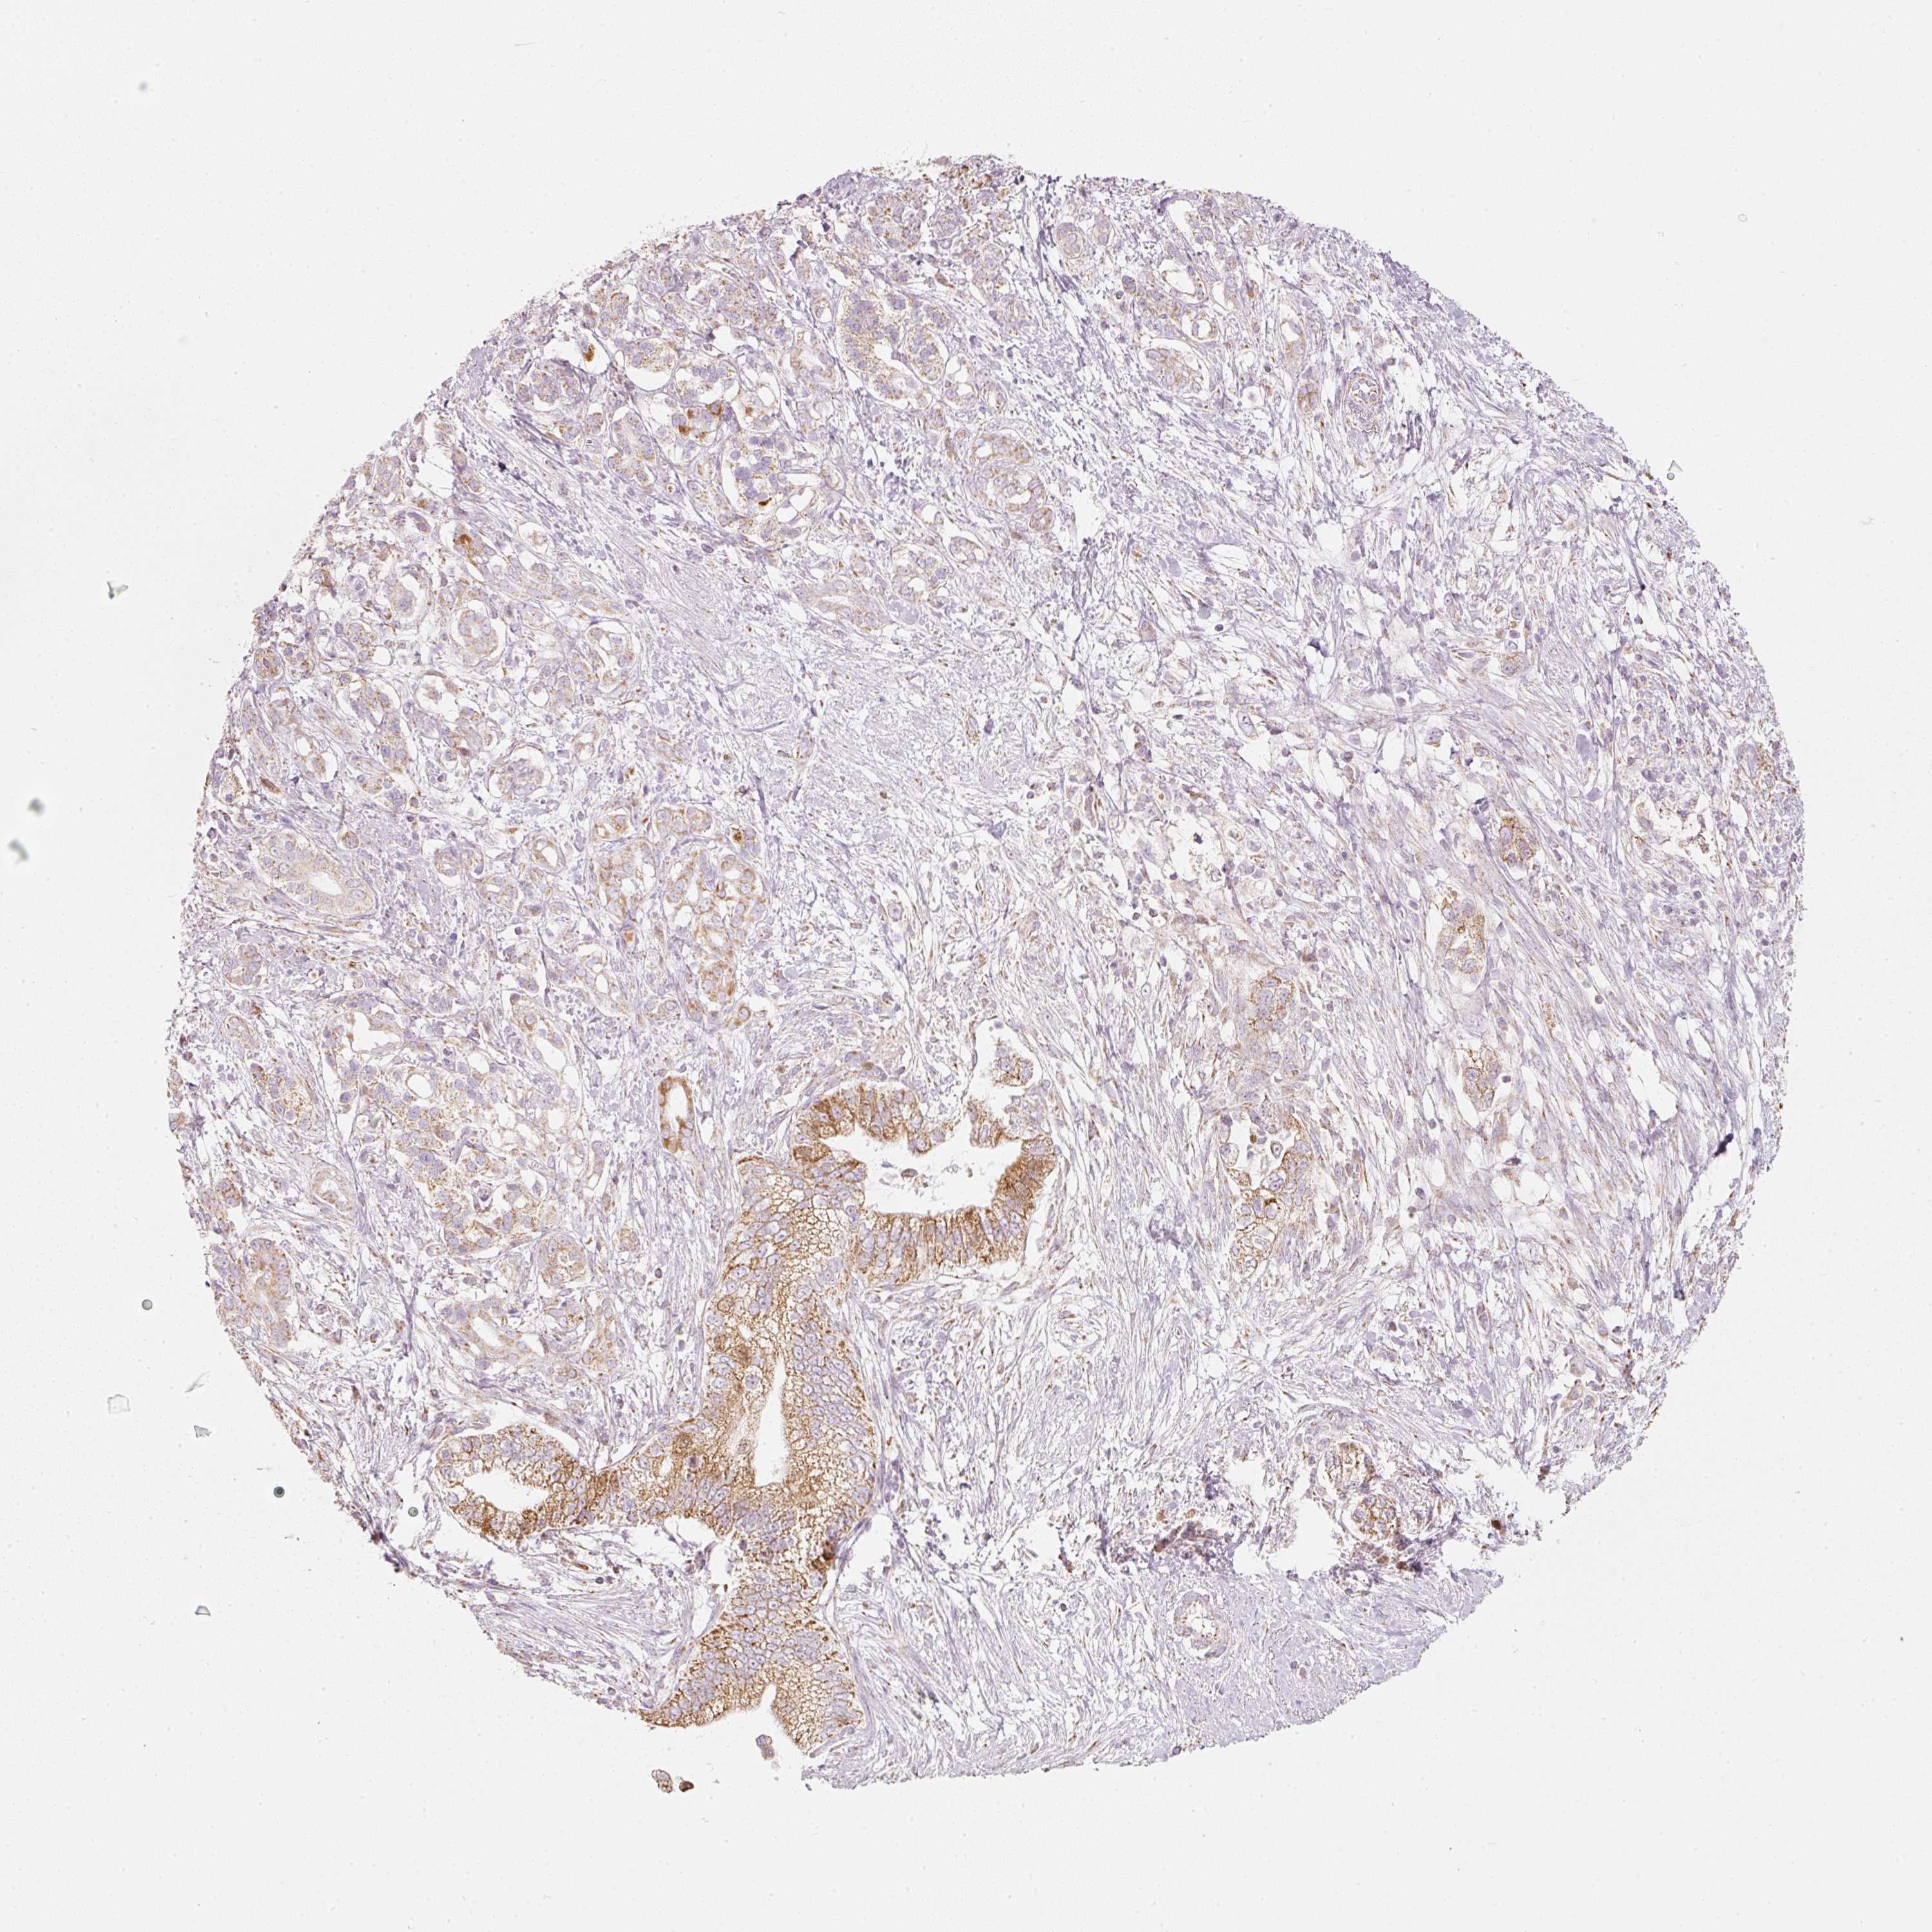

PANCREATIC CANCER - Protein expressioni

A mouse-over function shows sample information and annotation data. Click on an image to view it in a full screen mode. Samples can be filtered based on level of antibody staining by selecting one or several of the following categories: high, medium, low and not detected. The assay and annotation is described here.

Note that samples used for immunohistochemistry by the Human Protein Atlas do not correspond to samples in the TCGA dataset.

Antibody stainingi

Antibody staining in the annotated cell types in the current human tissue is reported as not detected, low, medium, or high, based on conventional immunohistochemistry profiling in selected tissues. This score is based on the combination of the staining intensity and fraction of stained cells.

Each image is clickable and will lead to virtual microscopy that enables deeper exploration of all samples and also displays staining intensity scores, fraction scores and subcellular localization as well as patient and tissue information for each sample.

Antibody HPA054422

Antibody HPA060360

Adenocarcinoma, NOS